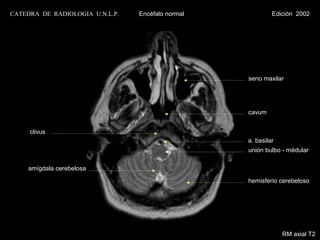

CATEDRA DE RADIOLOGIA U.N.L.P.   Encéfalo normal            Edición 2002

seno maxilar

cavum

clivus

a. basilar

unión bulbo - medular

amígdala cerebelosa

hemisferio cerebeloso

RM axial T2